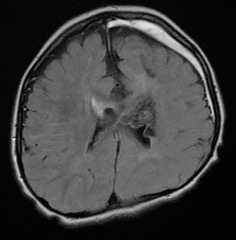

à l’inverse, une tumeur qui grossit peut devenir menaçante en empiétant sur le foramen de Monro (Cf. ci-contre), car il existe un risque de décompensation aiguë de l’hydrocéphalie.

il s’agit d’une tumeur bénigne qui ne métastase pas cependant il peut exister une récurrence tumorale : soit récidive vraie d’un reliquat tumoral, soit progression d’une autre tumeur

liée à la disposition génétique sous-jacente.

dans l’ensemble les résultats ontologiques sont donc médiocres (Cf. ci-contre), malgré la bénignité histologique de ce type tumoral.